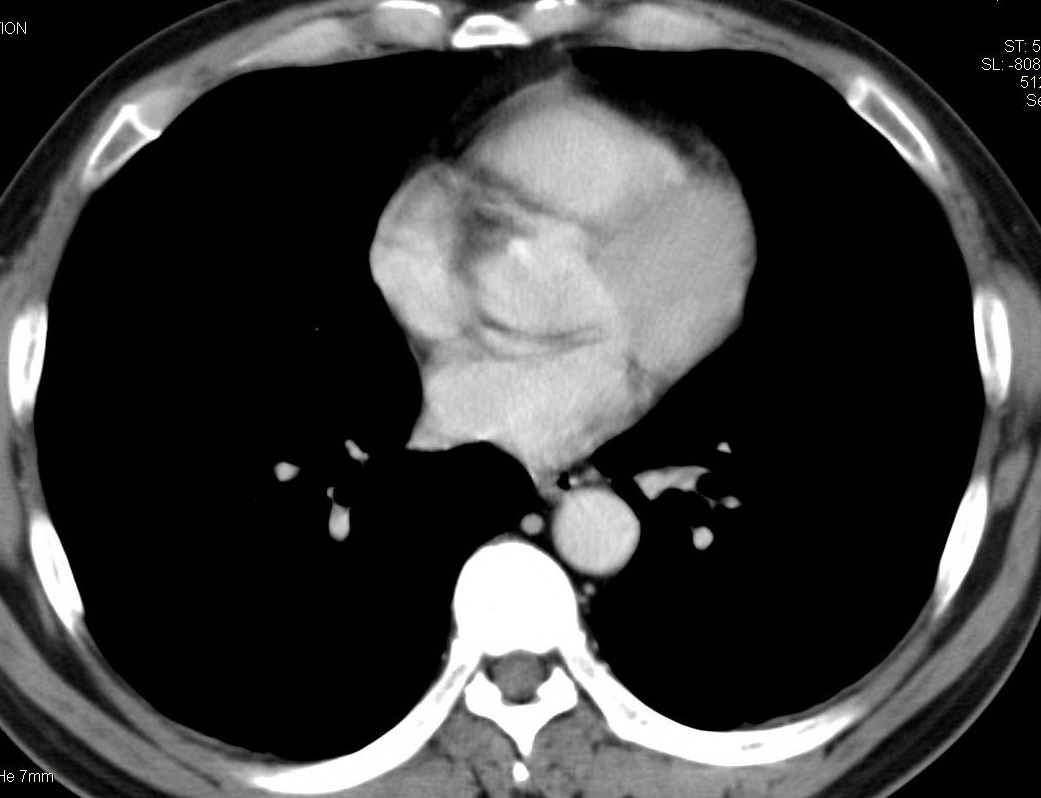

标题: CT15857:男性 58岁 咳痰带血 无发热 请各位大侠发表一下意见 [打印本页]

标题: CT15857:男性 58岁 咳痰带血 无发热 请各位大侠发表一下意见

两肺下叶肺纹理增多、增粗并呈“树芽状”改变。支气管扩张呈囊状,部分呈柱状改变。其周围可见散在的斑片样及条索样密度增高影,右肺下叶近叶间胸膜可见一形态不规则的高密度结节影,并与胸膜粘连。

考虑:支扩并发感染。

双肺多发炎性病灶,结核可能性大,建议抗炎治疗复查.右肺下叶前基底段结节灶,高度警惕肺癌可能

双肺间质性改变(间质纤维化?)伴支扩。右肺下叶有毛刺的小结节,考虑周围型肺癌可能性。